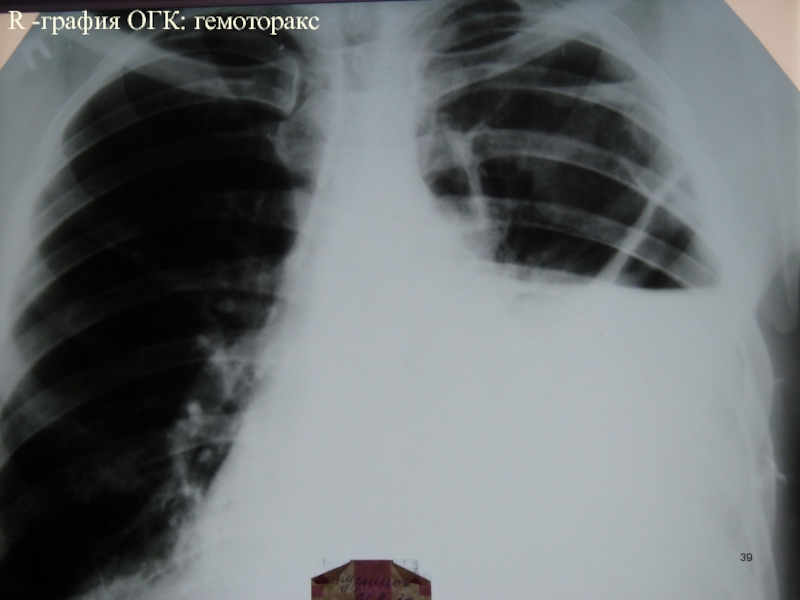

Слайд 39R -графия ОГК: гемоторакс

R -графия ОГК: гемоторакс